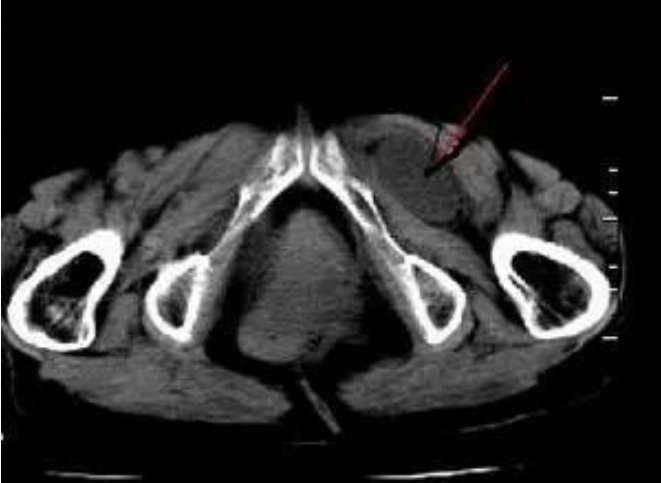

72岁的李奶奶半年来反复出现左侧大腿根部鼓包并疼痛,时常腹痛、腹胀、恶心,多次就诊未能确诊及根治。2025年2月19日,李奶奶因以上症状到外一科韩传学主任门诊就诊,CT检查发现左侧耻骨结节下方外侧有腹腔内容物疝出,局部卡压,考虑左侧闭孔疝可能。

闭孔(Obturator canal)是人体最大的骨性孔,大部分被腱性闭孔膜覆盖,仅在闭孔膜外上缘与耻骨上支之间有一裂隙称闭孔管。闭孔管位于闭孔的上方,其内走行闭孔动静脉、闭孔神经,是长度约2~3cm,宽度约0.2~0.5cm的真性管道。腹内脏器经闭孔管突出的疝称闭孔疝,因闭孔管管壁由骨质和坚韧的腱膜以及肌肉边缘组成,几无伸展性,故闭孔疝极易发生嵌顿和绞窄。(Obturator Hernia)。